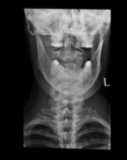

Acute calcific deposit on the enthesis of the longus colli muscle

The severe cervical spine pain prompted an emergency MRI examination, which showed a clear prevertebral inflammatory soft tissue process. On close inspection, a calcific deposit anterior to the dens axis can already be suspected on MRI (especially T2 or axial T1fs Gd+). The calcium depot is only shown very fluffy on X-ray and CT, suggesting an acute stage with precipitation/resorption of the calcific milk.

Therapy is initially conservative. Punctures and surgery of the calcific deposit can be done from endooral.

The longus colli muscle is a less common location of this condition, which should be referred to as HADD or acute calcific deposit. Also affected may be supraspinatus tendon and other tendons of the rotator cuff, extensor carpi radialis tendon, deltoid muscle, or hip adductors.